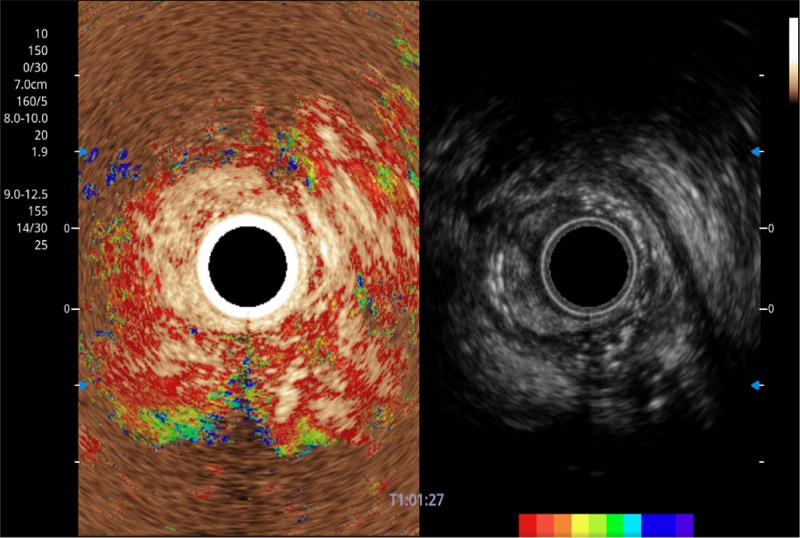

TIC时间强度分析曲线

具有四种造影成像效果

肝左叶和肝静脉的横截面